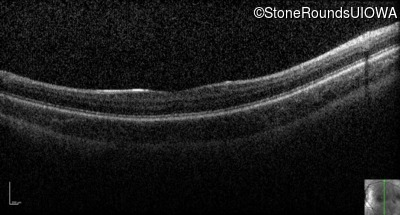

Optical Coherence Tomography - Left - 10/200

Exemplar / OCT Stack